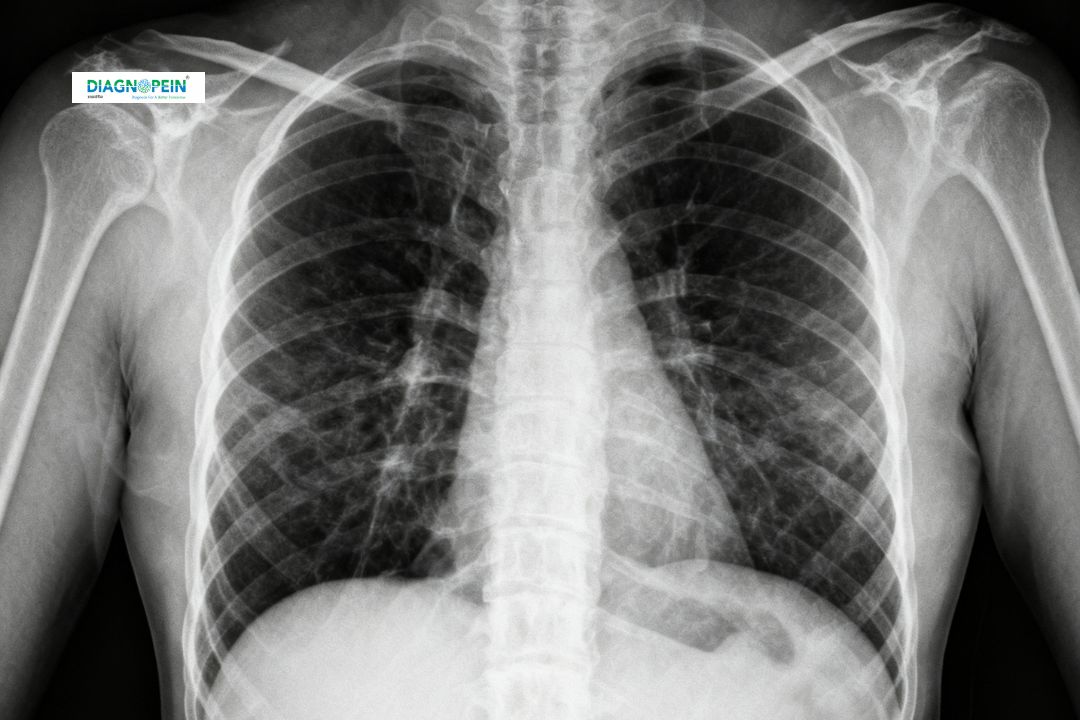

An X-Ray Chest PA (Posteroanterior) view is one of the most commonly performed diagnostic imaging tests used to assess the chest region. This imaging helps doctors visualize the lungs, heart, ribs, and surrounding structures in detail. It provides a clear and standardized image that assists in diagnosing respiratory conditions, cardiac enlargement, infections, and trauma-related abnormalities.

Parameters and Findings in X-Ray Chest PA

An X-Ray Chest PA report typically includes evaluation of:

1. Lung fields for any signs of infection, fibrosis, or scarring

2. Cardiac silhouette for size and shape

3. Pleural spaces for fluid or air accumulation

4. Bony structures including ribs and clavicle for fractures

5. Diaphragm position and clarity

Through these parameters, doctors can detect a wide range of chest diseases early and recommend proper treatment.